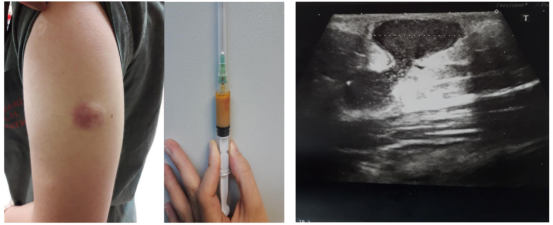

22岁女性,因接种部位肿胀而入院。患者在3周前实习期间接种了Td疫苗,接种后4天注射部位开始肿胀。该疫苗是一种含有铝佐剂的类毒素疫苗(泰达蒂夫;土耳其药物和血清工业公司)。体格检查显示,肿块大小约6×6cm,呈起伏状,但无疼痛,红肿(图1)。口服阿莫西林/克拉维酸(每日2×1g)和局部抗生素(2%乳膏,夫西地酸2×1)10天。

患者无免疫抑制疾病和复发感染史。在既往病史中,患者接受了所有儿童时期的疫苗接种,没有出现任何严重的副作用。入院时无外伤史,无发热,检查无淋巴结肿大。实验室检查显示,白细胞总数为6500个/McL,其中70%为中性粒细胞,而C3、C4、免疫球蛋白(Ig)a、IgM、IgG、IgE、沉降率和C-反应蛋白均在正常范围内。人类免疫缺陷病毒血清学阴性。超声检查发现皮下有两个相互连接的脓肿,没有累及肌肉组织(图2)。

图1. 波动性无痛肿块,无发热,红肿

图2. 皮下有两个相互连接的脓肿